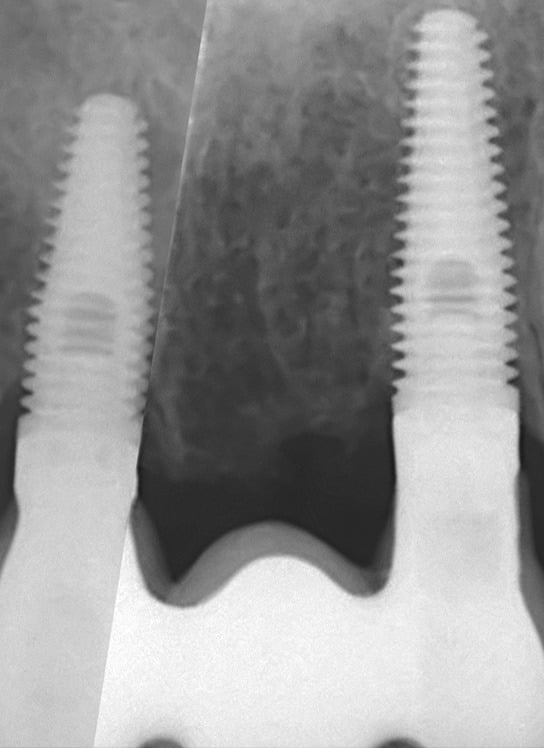

The fixture (titanium screw) replaces the function of a natural tooth root. Your jawbone attaches to the titanium threads of the fixture, providing a completely stable foundation for the new crown – a process known as osseo-integration. It usually takes twelve weeks for the bone to securely bond to the entire fixture surface.

A dental implant is simply a metal screw that is placed into the jawbone. It acts as an anchor for a false tooth or a set of false teeth. It functions very much like the root and crown of your natural teeth.

Your natural teeth are stable biting and chewing surfaces because your jawbone supports them. This is also true of dental implants. Successful dental implants become firmly embedded in the jaw through osseointegration, a natural process where the bone grows onto the implant surface.